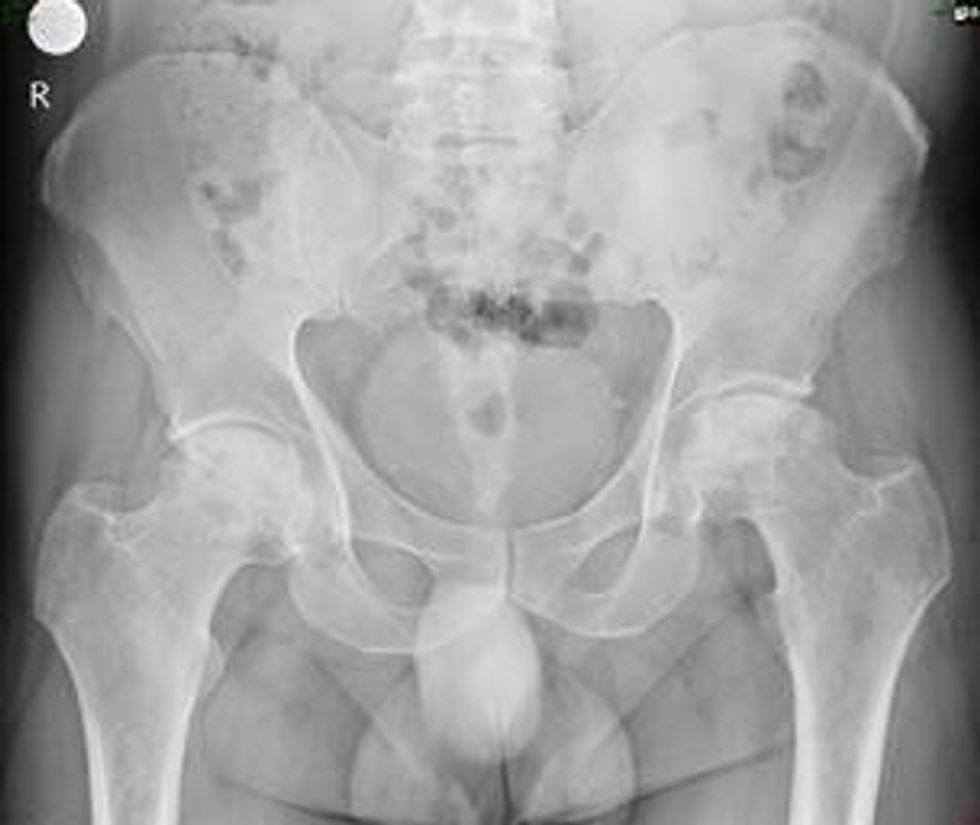

Koksartroza është një sëmundje degjenerative-rigjeneruese e këllkut dhe është një nga sëmundjet më të zakonshme të aparatit lokomotor (sistemit muskuloskeletor). Bëhet fjalë për osteoartritin, domethënë një sëmundje e theksuar kronike dhe progresive që shfaqet zakonisht në vitet e mëvonshme, por nuk i anashkalon as të rinjtë. Koksartriti do të thotë dëmtim i kërcit të nyjes së këllkut. Shfaqja e dhimbjes është simptoma kryesore dhe më e zakonshme, dhe shoqërohet me kufizim të lëvizshmërisë së nyjes, paqëndrueshmëri të saj dhe hipotrofi të muskujve përreth.